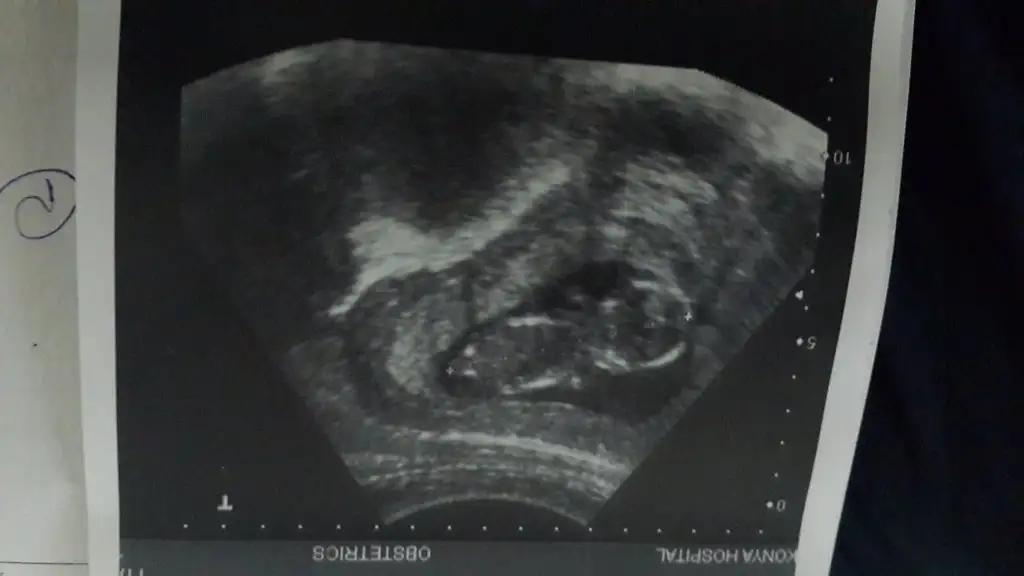

kızlar selam bugün 2li test için tekrar gittim doktoruma.. benimki hala yüzüstü yatıyordu ama neyseki bu sefer ölçümleri alabildik.. bebişim 7 cm olmuş ensesi de 1,7 çıktı.. doktor gayet güzel dedi.. ama yüzüstü yattığı için cinsiyetle ilgili hiçbirşey söyleyemedi.. umarım doğmadan önce kızımız mı oğlumuz mu olcak öğrenebilirim :)) ultrason fotosunu buraya da yüklüyorum :) tahminlerinizi bekliyorum kızlarcım :)

Eklentiler

• IMG_7589.webp

IMG_7589.webp

30,3 KB · Görüntüleme: 139

• IMG_7590.webp

IMG_7590.webp

20 KB · Görüntüleme: 118